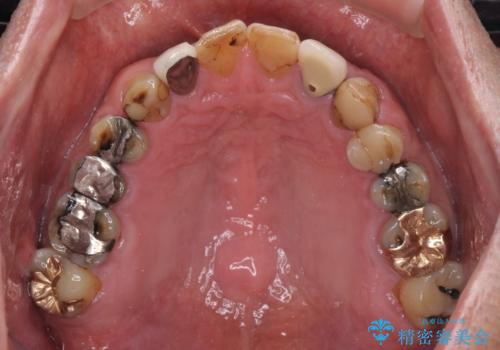

- コンポジットレジンやクラウンなど、様々な医院で治療を受けたために、統一感がなくなってしまった前歯を綺麗にしたいとのことで来院された患者様です。

当初は前歯6歯をオールセラミッククラウンで補綴する予定でしたが、前歯が綺麗に仕上がったことで、奥歯まで延長して補綴することとしました。